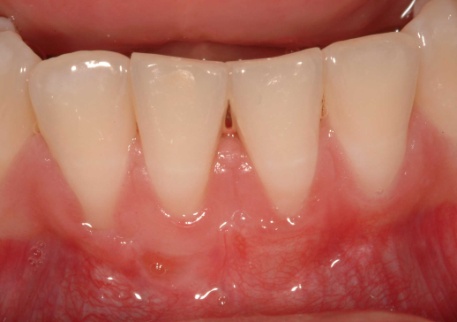

Repair following a gum graft procedure